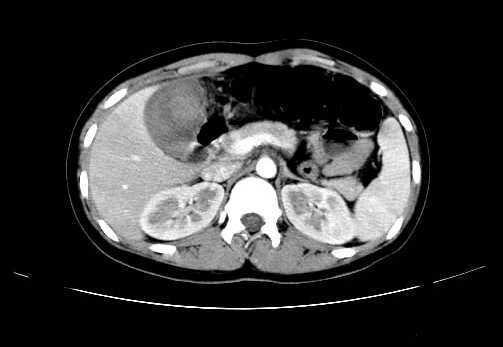

女 16岁  右上腹痛一天,无其他不适

肿块最大径位于十二指肠降段与水平段移行处,并且与肝脏压迹呈“0”形征,可以考虑位于肝外并与胃肠道关系紧密,考虑胃肠道间质瘤(gist)可能较大,须除外神经节起源肿瘤。

肿块与十二指肠关系密切,支持间质瘤诊断.肝脏与结肠均为受压改变.

右下腹巨大肿快,密度不均匀,内见坏死低密度区,边界清楚,与周边胀器明显有分界,未见强化,多考虑来源于间叶组织的良性肿物.

我坚决反对您的观点,该病例定位:横结肠肝曲与升结肠之间的肠系膜及部分肠壁。请看下图:

病灶巨大,少部分向肠腔内生长,大部分向长腔外生长。其密度不均匀,增强显示明显不均匀强化,并见有大片状始终不强化的不规则坏死液化区。虽然病灶中上部形态尚可,病人又如此年轻,但中下部形态、密度、强化特点强烈提示为恶性病灶。综上,我考虑本病例为:恶性胃肠道间质瘤。